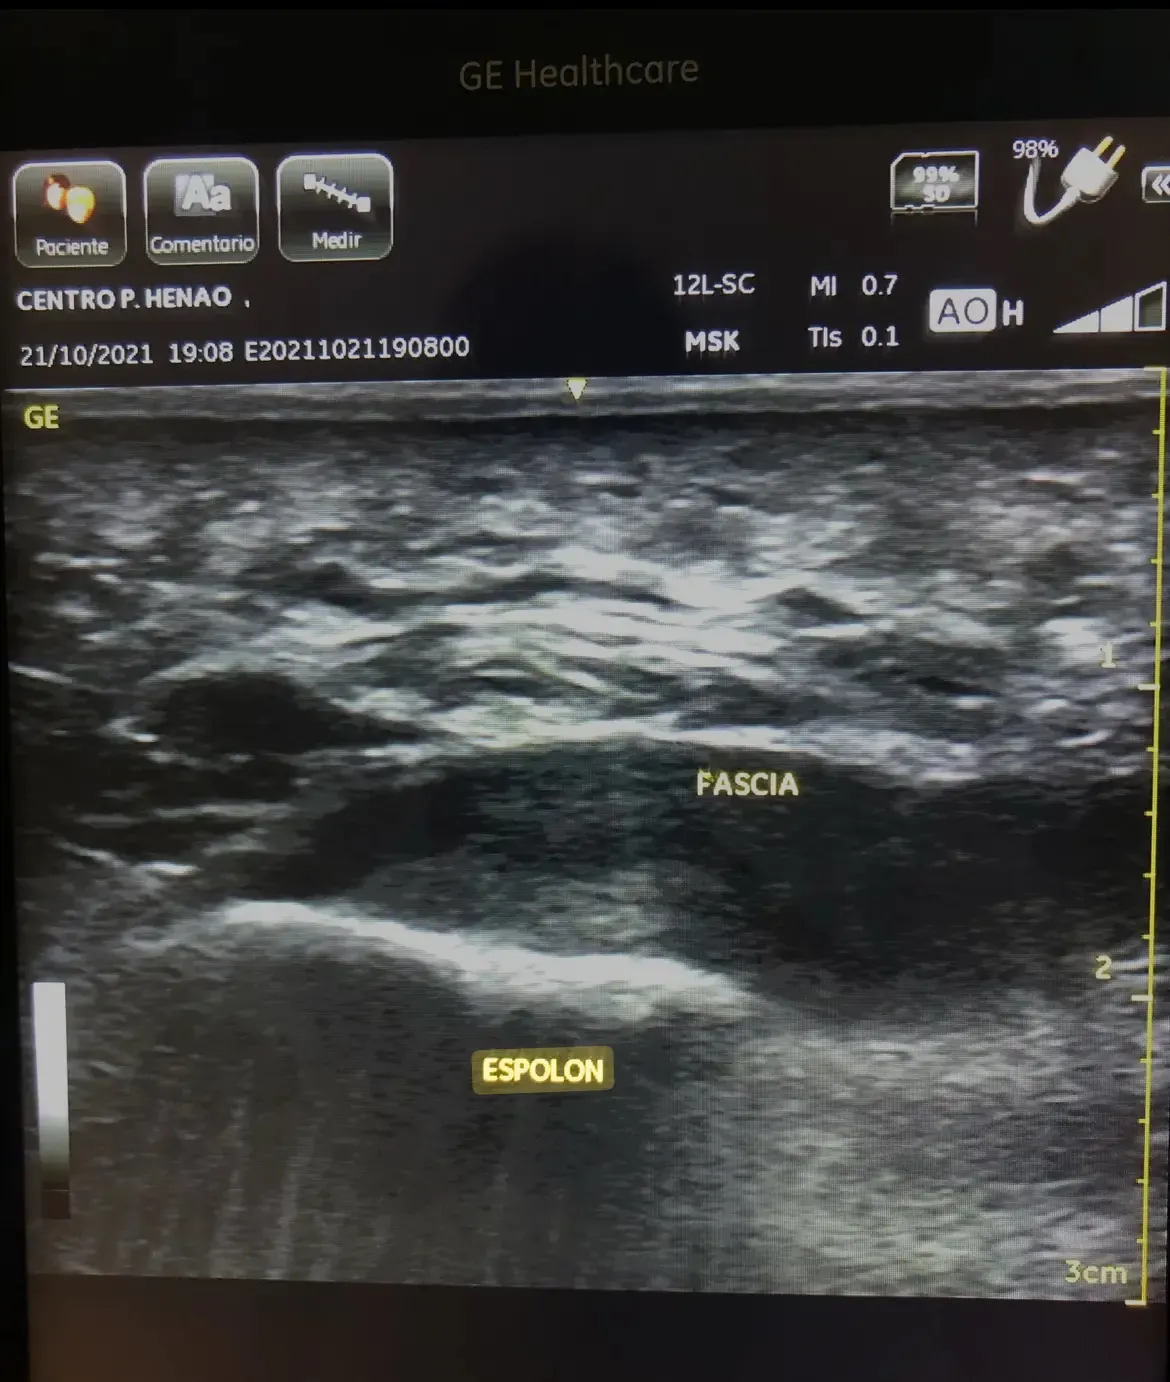

Ondas de Choque para Espolón Calcáneo en Bilbao

Tratamiento con ondas de choque para espolón calcáneo en Bilbao. Abordamos la causa real del dolor de talón con tecnología avanzada y diagnóstico ecográfico.